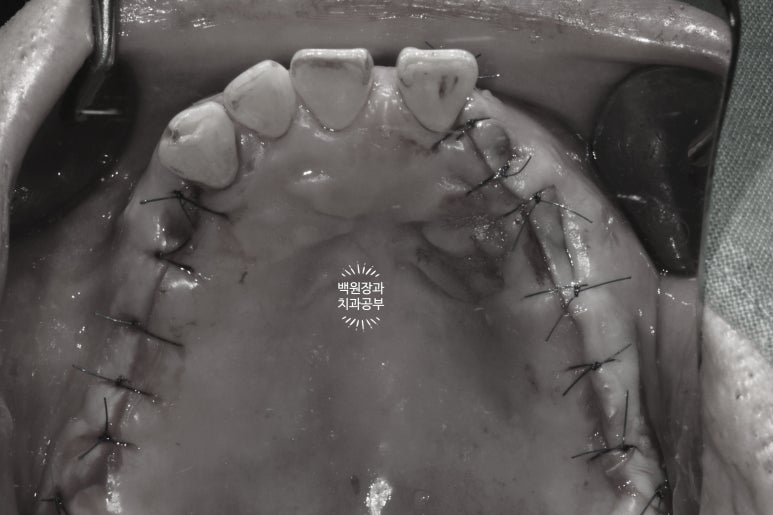

수술 하고 봉합 후 사진입니다!

으... 너무 아파보인다 ㅠㅠ 라고 많이들 생각하시지만,

실제로 마취를 넉넉히 하고 하기 때문에 하나도 아프지 않습니다........

보통 이를 빼는 것보다 임플란트 수술이 덜 아프다고들 하세요!